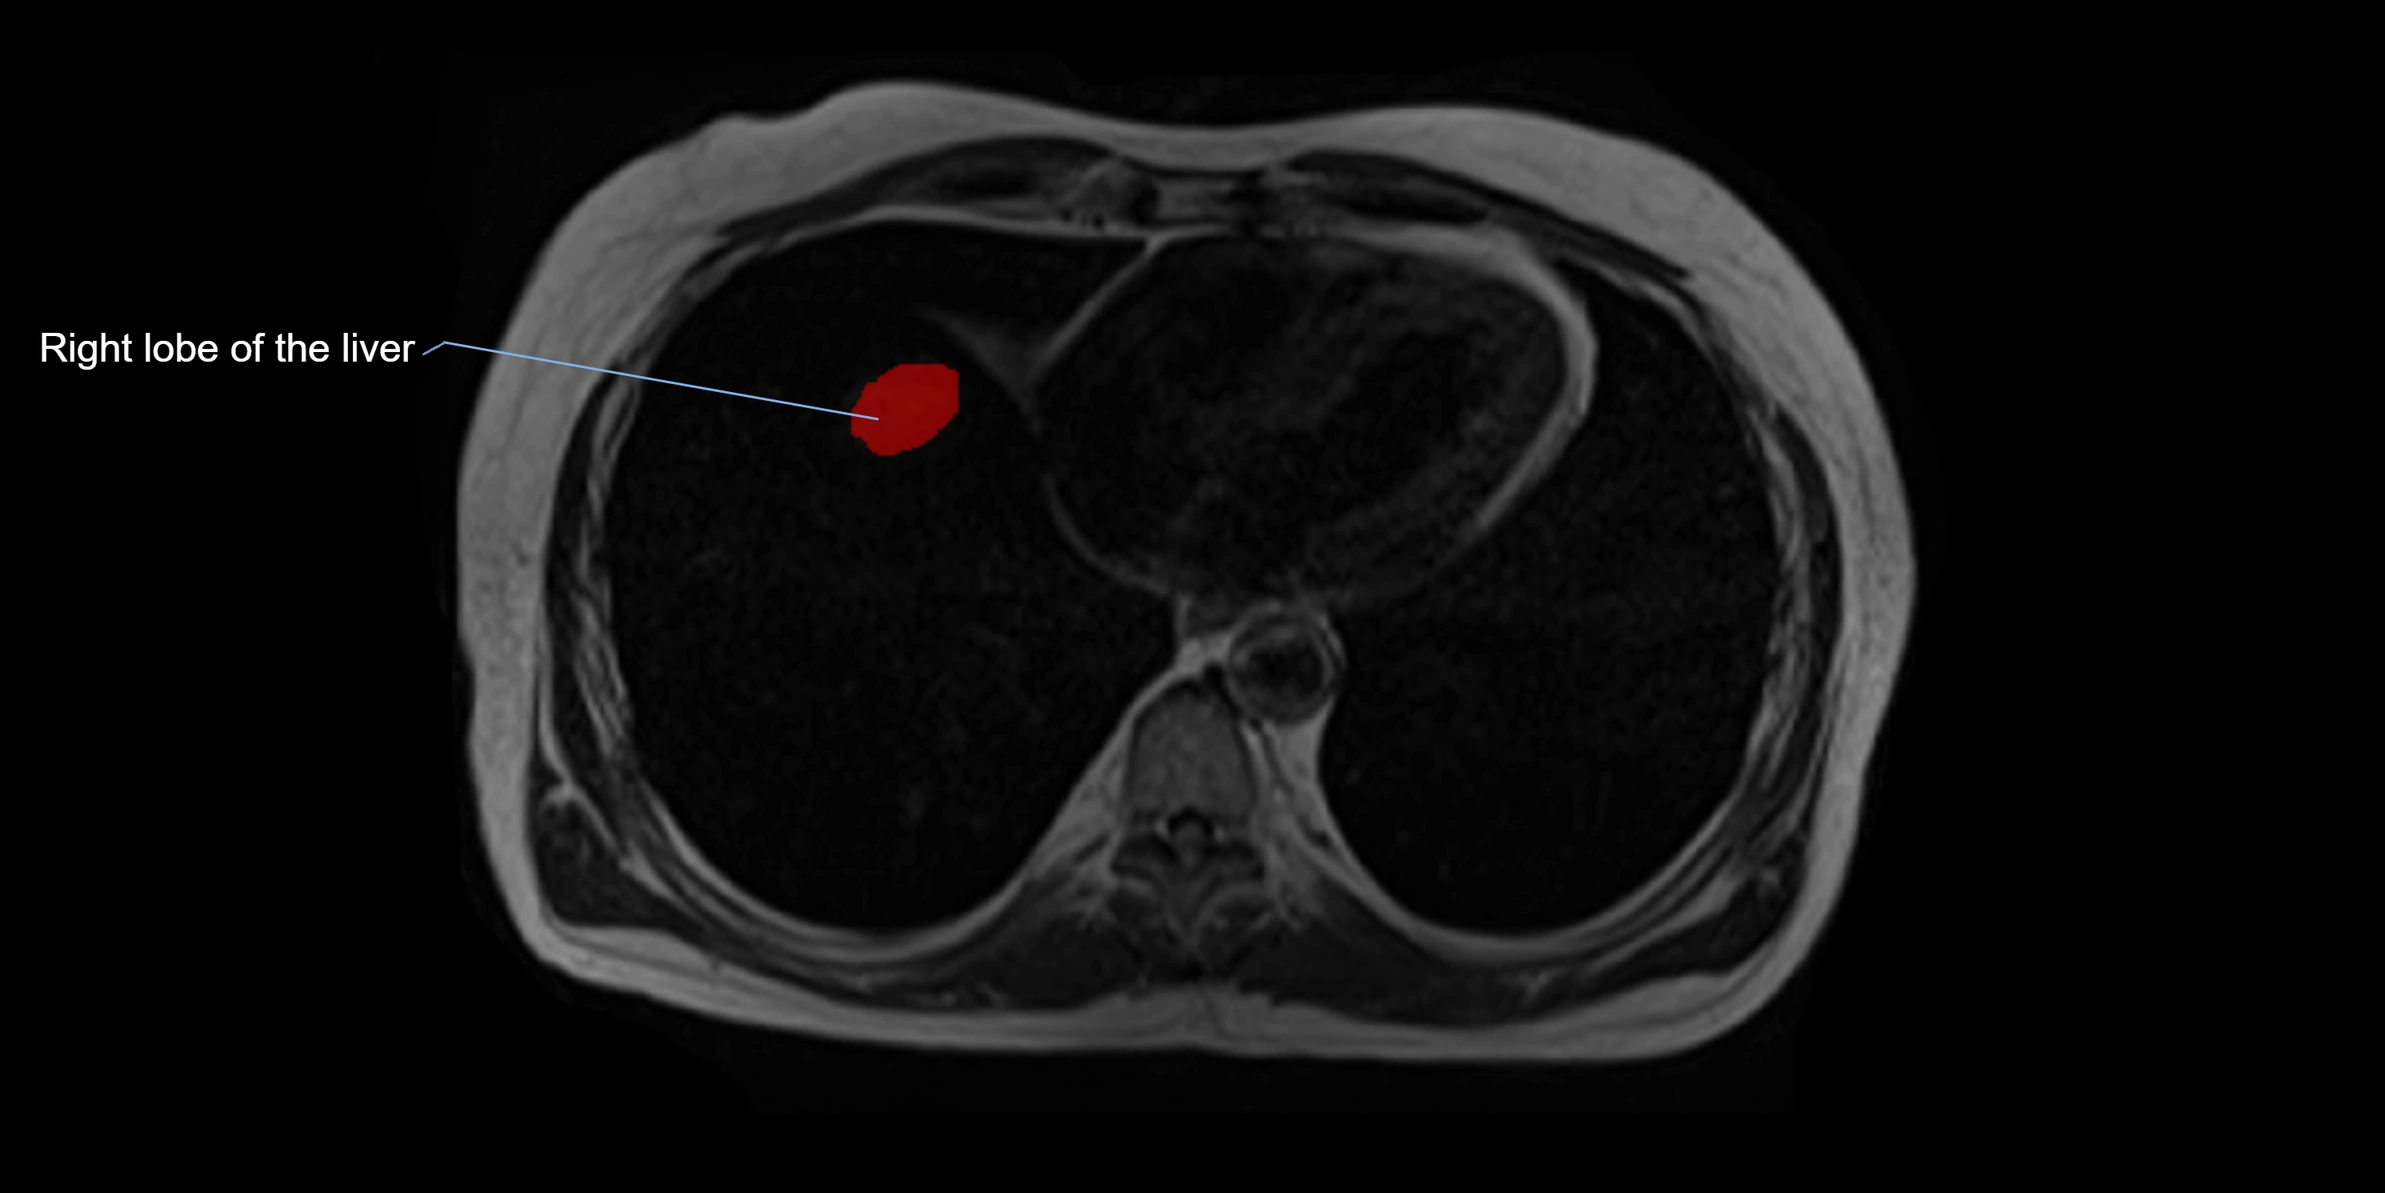

MRI image

image